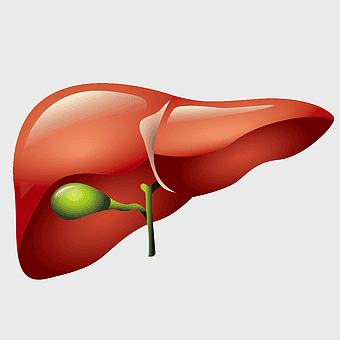

human liver anatomy, medical imaging liver, liver radiology scan, human digestive system liver, abdominal organ visualization, internal anatomy illustration, liver health diagram -

liver illustration, human liver cartoon, cartoon liver image, liver organ diagram, liver anatomy visual, medical liver graphic, liver health depiction -